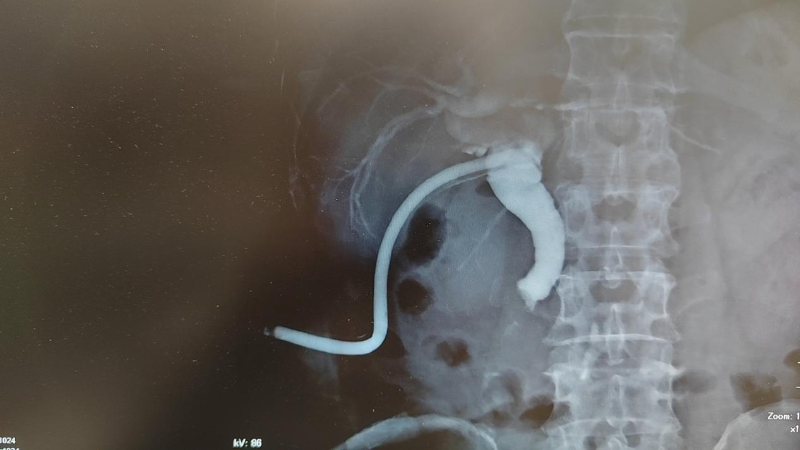

图片 1

(入院后术前T管造影,提示胆总管下端重度狭窄)